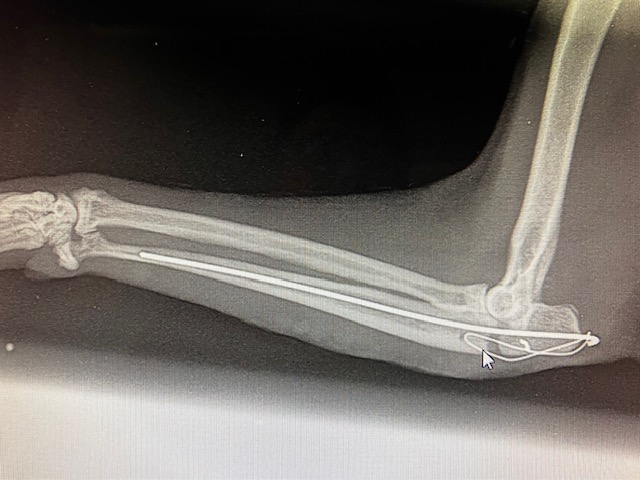

Nous abordons l’articulation du coude par voie latérale. Un clou de Steinmann de 1,2 mm est introduit par voie rétrograde dans le foyer de fracture, dans l’about proximal olécranien, puis repoussé dans la cavité médullaire de l’about distal de l’ulna sur la majorité de sa longueur. Cela permet de réduire la fracture et de mettre en compression les 2 abouts osseux.On prend des précautions pour ne pas trop léser le tendon du triceps brachial. La broche est courbée proximalement, pour éviter les lésions de la peau et permettre un retrait ultérieur de l’implant.

Pour augmenter la solidité, éviter que le foyer de fracture ne s’écarte, nous posons en complément un Fil de cerclage en 8, passant dans un orifice osseux percé dans l’about ulnaire distal puis s’accrochant sur l’extrémité courbée de notre broche, en passant sous le tendon du triceps. Cette technique de Haubanage met en compression le foyer de fracture et assure une contention supplémentaire, en limitant aussi partiellement les mouvements de rotation.

Les tissus mous et la peau sont suturés de façon classique.Pour compléter la contention, nous effectuons un pansement de Type Robert-Jones, légèrement compressif et assurant un bon maintien de la fracture stabilisée chirurgicalement.